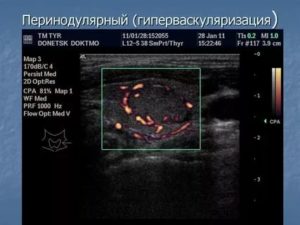

Перинодулярный кровоток (васкуляризация) – сочетание слов, которое иногда упоминается врачом эндокринологом в истории болезни, и применяется этот термин для описания патологии, во время проведения допплерографии, в том числе и при исследовании узла щитовидной железы.

Диагнозом, это словосочетание назвать нельзя, поскольку оно является описанием картины, которую видит на мониторе специалист, при проведении цветного допплеровского картирования (ЦДК) или энергетического (ЭДК).

Образование слова «перинодулярный», происходит из латинского языка, а именно, из 2-х слов: peri (вокруг, около) и nodus – означающее «узел».

Следуя переводу, можно понять, что перинодулярным можно считать васкуляризацию, которая располагается по внешней части новообразования, то есть – на периферии.

Сам термин, не может говорить о характере обнаруженного узла щитовидки, а именно, доброкачественное это образование или нет. Поэтому, бросаться в панику – не стоит.

Перинодулярный кровоток

При таком виде васкуляризации обнаруживается, что стенки новообразования имеют хорошее кровоснабжение, но внутри его, сосудов не наблюдается.

Статистика говорит о том, что около 85% обнаруженных узлов с периферийной васкуляризацией, имеют доброкачественный патогенез. Капсула, обычно наполнена жидкостью или гелеобразным содержимым (коллоидом).

Перинодулярный кровоток узла щитовидной железы

Перинодулярный кровоток узла – сосуды находятся за пределами, а в самом узле щитовидной железы их нет. Признак доброкачественности в 85% случаев, характерен для неактивных образований, встречается и при кистах.

Перинодулярная васкуляризация

Происходит активное кровоснабжение стенок узла, но внутри образования кровеносных сосудов нет. Примерно в 85% случаев это говорит о том, что опухоль щитовидки доброкачественная, а внутри капсулы находится жидкость либо коллоид (гелеобразное содержимое).

В редких случаях такую картину при ЦДК дают злокачественные новообразования на начальной стадии, когда еще не запустился ангиогенез. При этом и доброкачественные, и злокачественные опухоли будут гипоэхогенными за счет жидкости внутри.